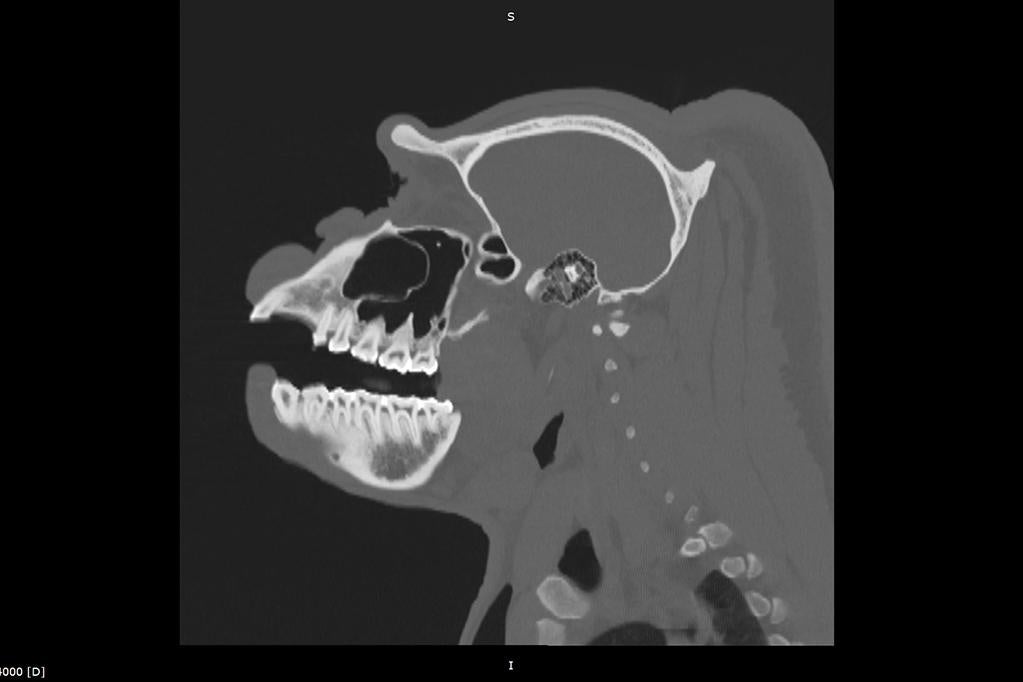

Much like your visits to the dentist, animals undergo everything from detailed tooth charting to advanced imaging such as X-rays or CT scans, helping identify problems before they could potentially become more serious conditions. Treatments can include cleanings, root canals, or extractions, providing each animal with care and support for their long-term health.

Take lions, for example. Lions rely on their powerful teeth as their multi-purpose tools. Their teeth are essential for gripping prey, devouring meals, and even baring them in defense and fighting. When Bo, a lion who lives at the Safari Park, recently came in for his routine exam, our team recognized that his “tools” needed special attention. The team performed a root canal on Bo’s right mandibular (lower jaw).

Another lion, named Ernest, was also recently treated as he needed root canals on two teeth—care neither big cat would have gotten in native habitat. Both lions were quickly on their way to recovery thanks to our team’s early action and expertise.